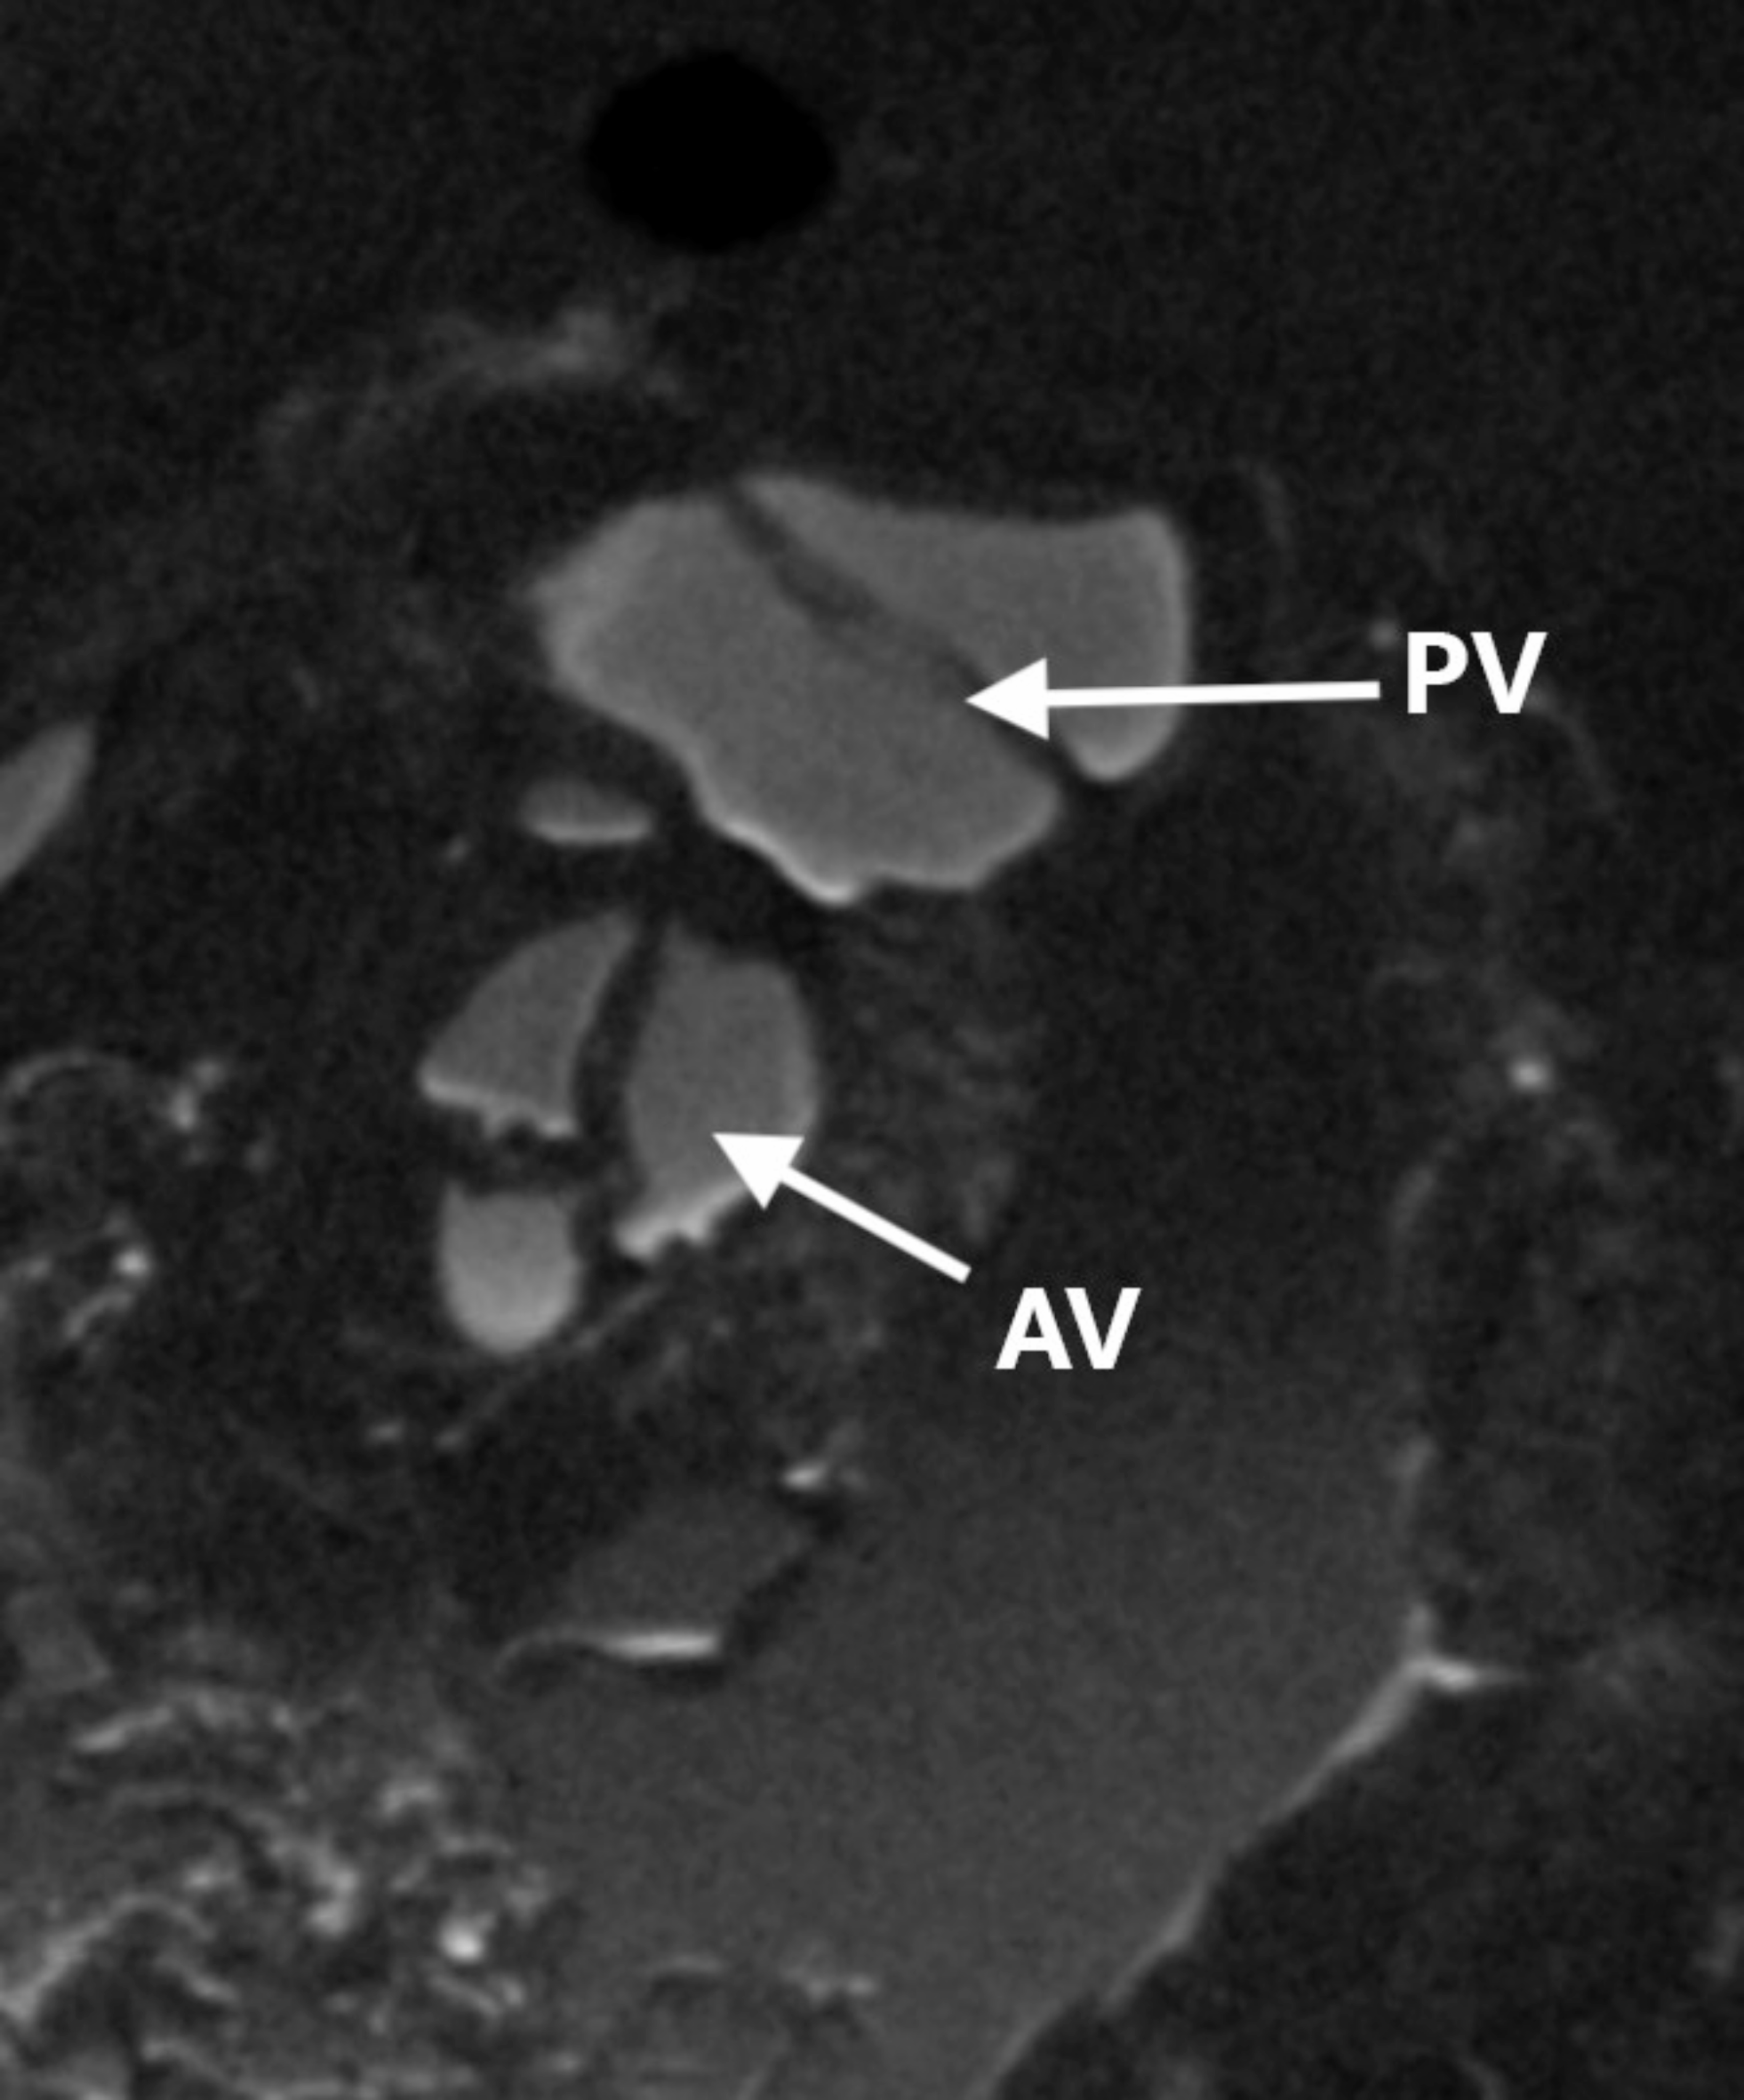

Fig. 5

Puppy #3. Cross-section through the heart at the level of both great arterial valves. Bicuspid pulmonary valve located on the left and ventrally, aorta on the right and dorsally. Correct spatial relationship. PV pulmonary valve, AV aortic valve.